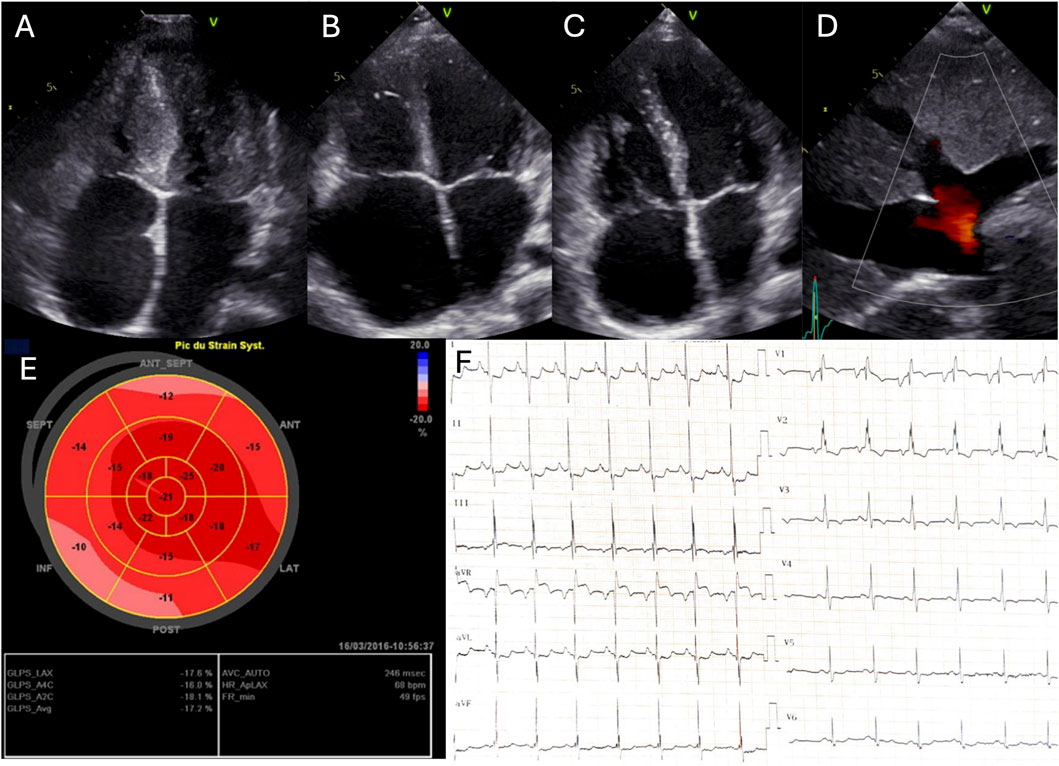

Electrocardiograms (ECGs) showed bi-atrial hypertrophy and repolarization abnormalities including ST depression secondary to subendocardial ischemia, in all patients (Figure 1F). In addition, we observed a borderline QT prolongation (450 m) in patient 3, though no ventricular arrhythmias were detected, and there was no family history of such events. 24-h Holter-ECG revealed ectopic atrial tachycardia in patient 1 whereas symptomatic typical atrial flutter and then polymorphic atrial tachycardia was clinically documented in patient 2.

Figure 1

Figure 1. Echocardiography and electrocardiogram. A, B, C Four-chamber echocardiogram at end-diastole of patient 1 (A), patient 2 (B) and patient 3 (C); (D) Subcostal echocardiographic view of patient 2; (E) LV strain longitudinal of patient 3; (F) Electrocardiogram of patient 1.

3.2 Echocardiography and CMR

All patients exhibited restrictive cardiomyopathy, with ventricular hypertrophy in two patients (patient 1 and 3) (Table 1; Figure 1). Echocardiography revealed restrictive physiology of the left ventricle, reduced diastolic compliance, bi-atrial enlargement and normal left ventricular systolic function. Right-sided filling pressures were elevated in all patients. Patient 2 and three displayed right-dominant restrictive cardiomyopathies, with significant right atrial dilation.